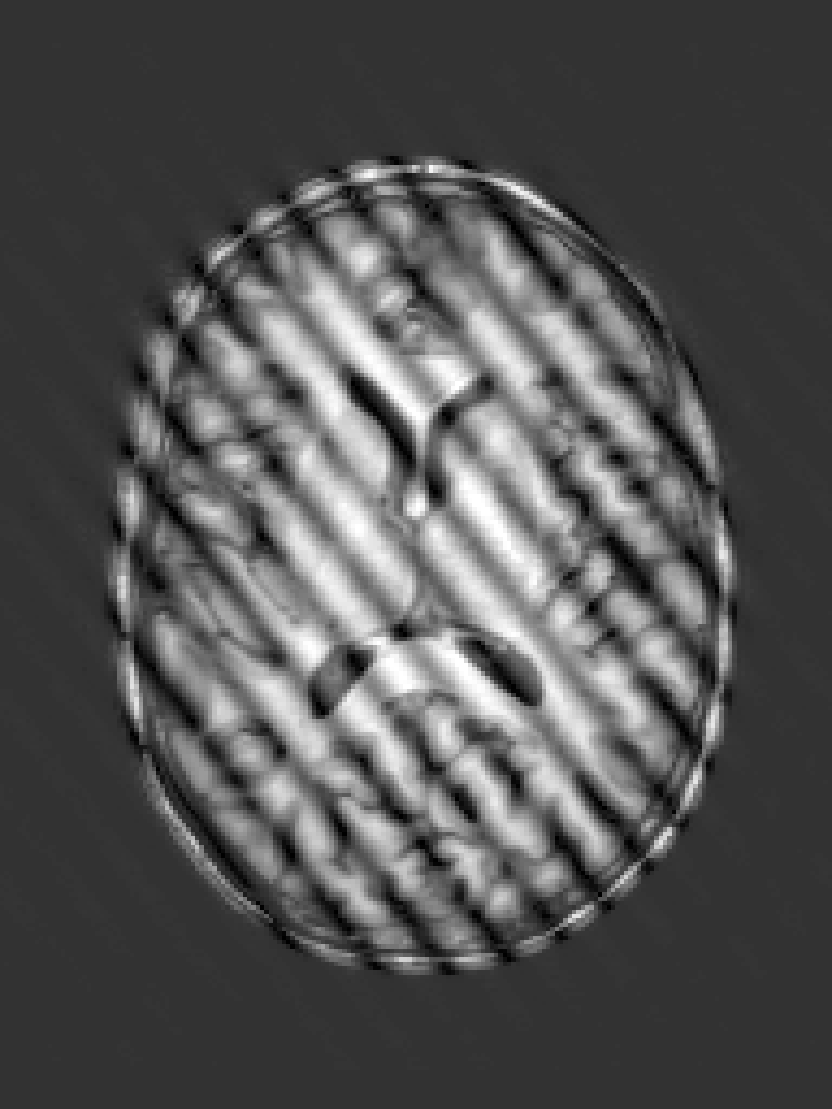

During the training of each segmentation CNN, randomised k-space augmentations affecting image quality are applied on-the-fly. The types of augmentation are designed to emulate realistic MRI artefacts and are detailed below. Each augmentation is applied to the k-space by computing the 3D Fast Fourier Transform (FFT) of the input image volume, modifying the k-space, and then computing the inverse 3D FFT, taking the magnitude image scaled between 0 and 1 as input to the network. All augmentations are applied at a rate such that roughly 50% of images seen by each CNN during training contain artefacts. The order in which k-space augmentations are applied is important to best reflect the MR imaging process, with for instance RF spike noise lowpass filter/k-space sampling. In addition to k-space augmentation, image rotation, scaling and flipping augmentations in all three axes are applied by default to all images, as well as bias field augmentation to account for variation in image intensity across samples.

RF spike artefact is characterised by dark stripes over the image, as shown in Figure 3 a) caused by

the convolution of spikes in k-space of very high/low intensity during the FFT (Zhuo and Gullapalli, 2006). For augmentation we sample uniformly its location in k-space which specifies the angle/frequency of stripes, and its magnitude which defines the intensity of the stripes from between 1 and 10 times the maximum magnitude of the original k-space.

k-Space noise augmentation involves injecting Gaussian noise into the k-space, as shown in Figure 3 b), to model Rician noise in the image domain. The desired signal-to-noise ratio (SNR) of the image is uniformly sampled between [-10dB, 20dB] and the corresponding amount of complex noise with zero mean and equal variance is added to the k-space.

Blurring artefact can be observed when acquiring data at lower resolution along an axis prior to resampling. Low-pass filter applied by truncating the k-space along one or more randomly chosen axes as shown in Figure 3 c) can simulate this effect. The width of the filter defines the equivalent downsampling ratio, which is uniformly sampled between 2 and 12.

Aliasing/wrap artefact occurs when the imaging field of view (FOV) is smaller than the anatomy being imaged. This is retrospectively simulated by masking out k-space lines as shown in Figure 3 d). A proportion of k-space lines are either randomly masked uniformly, or at regularly spaced intervals, along a random axis that defines the wraparound direction.

Motion artefact occurs when the patient moves during the scanning process, and can manifest as blurring, ringing or ghosting effects in the image, depending on the amount and timing of patient movement with regards to the k-space scan trajectory. To simulate motion artefacts, we use the implementation from Shaw et al. (2020). The input image volume is resampled according to a randomly sampled movement model, defined by a sequence of ‘demeaned’ 3D affine transformations. Their respective 3D Fourier transforms are combined to form a composite k-space, which is transformed back to the image domain producing the final artefact volume containing motion.